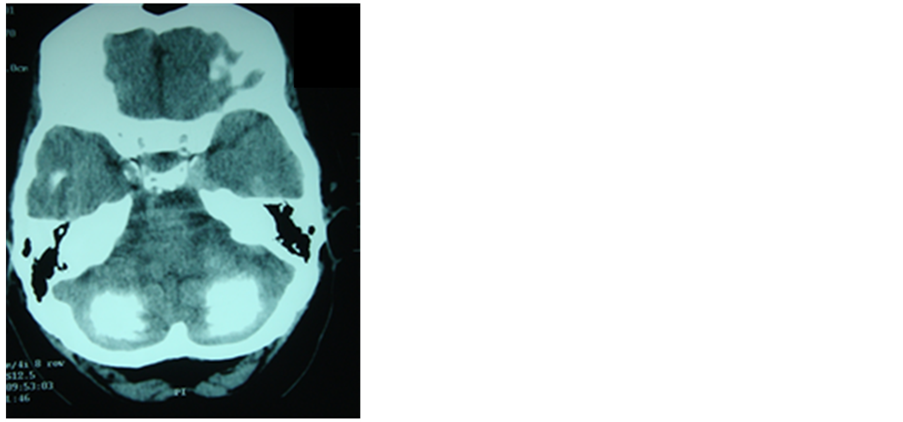

Epilepsy associated to later brain calcifications has been described as a rare entity in celiac disease [42] , (Figure 2) where the reduction of secondary folate levels due to poor absorption is considered the reason of such calcifications [43] ; however on another theory silica toxicity seems to play an important role in the pathogenesis both on the calcifications and on the seizures [44] .

Figure 2. CT scan of patient admitted for out- patient service by epilepsy with gastrointestinal symptoms in the course of celiac disease.